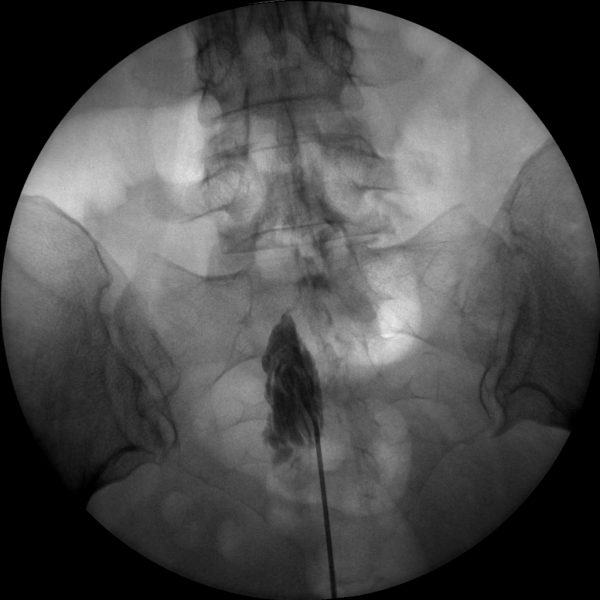

The vascular package comes standard with Skan-C that enables clinics and ambulatory surgery centers to perform a wider range of procedures, including DSA and roadmap. These packages typically include specialized imaging modes, tools, and software upgrades that are specifically designed for vascular interventions.

Some of the DSA procedures in which Skan-C is highly effective are

Cerebral & peripheral angiography

Cerebral & peripheral angioplasty

Stenting

Thrombectomy

Embolization

DSA and Roadmap built into the system is a significant advantage for clinics and ambulatory surgery centers, both from the point of view of patient care and cost benefits. Instead of referring patients to larger hospitals or specialized facilities, these facilities can provide comprehensive care in-house, leading to potential cost savings for the patients and the healthcare system